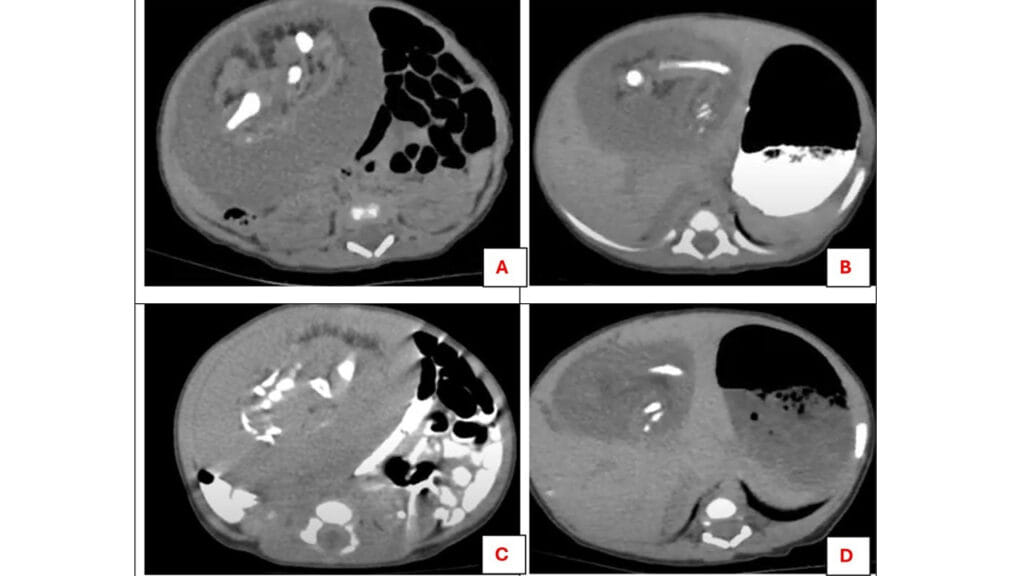

అప్పుడే పుట్టిన నవజాత శిశువు గర్భంలో పరాన్నజీవి కవల పిల్లలు పెరుగుతున్నట్లు వైద్యులు గుర్తించి గట్టి షాక్ తిన్నారు. ఆ ఆడబిడ్డ 11 రోజుల వయసులోనే ఆస్పత్రిలో చేరింది. ఆమె కడుపు ఉబ్బిపోయి.. పరిమాణం భారీగా పెరుగుతుండటంతో కుటుంబ సభ్యులు తీవ్రంగా ఆందోళన చెందారు. డాక్టర్లు వెంటనే అల్ట్రాసౌండ్ చేయగా 8*6 సెంటీమీటర్ల పరిమాణంలో ఉన్న ఓ ముద్దను కనుగొన్నారు. ఆ ముద్ద మృదువుగా.. అలాగే స్థిరంగా పెరుగుతుండటం గమనించారు. అలాగే పాప ఊపిరి తీసుకుంటున్న సమయంలో అది అస్సలు కదల్లేదని గుర్తించారు. డౌట్ వచ్చిన డాక్టర్లకు మరోసారి కాంట్రాస్ట్-ఎన్హాన్స్డ్ కంప్యూటెడ్ టోమోగ్రఫీ స్కాన్ తీయగా.. ఈసారి పొడవైన ఎముకలు, పక్కటెముకలు, వెన్నుపూస, కటి ఎముకలు, మృదు కణజాలాలను పోలి ఉండే వికృతమైన అస్థిపంజర ఆకారాన్ని చూపించింది.

వైద్యులు దానిని పిండంలో పిండం పెరుగుతున్నట్టుగా నిర్ధారించడమే కాకుండా.. ఇది చాలా అరుదు అని అన్నారు. శరీరం లోపల వికృతమైన పరాన్నజీవి కవలలు అభివృద్ధి చెందినప్పుడు సంభవించే చాలా అరుదైన క్రమరాహిత్యంగా గుర్తించారు. శస్త్రచికిత్స నిర్వహించి.. సుమారు రెండు గంటల అనంతరం వికృతమైన ఆ ఆకారాన్ని డాక్టర్లు తొలగించారు. మైక్రోస్కోపిక్ పరీక్ష ద్వారా దానిని ‘పరిణతి చెందిన పిండ కణజాలం’ ఉందని.. చర్మం, ప్రేగులు కూడా ఉన్నాయని డాక్టర్లు తేల్చారు. ఆశ్చర్యమేమిటంటే.. ఆ పాపకు ఎలాంటి లక్షణాలు కనబడలేదు. బాగానే తిన్నది అని అన్నారు. ఆసుపత్రిలో చేరిన నాలుగు రోజుల తర్వాత ఆ పాప కడుపులోంచి ఆ ముద్దను తొలగించారు. అసాధ్యమైన రీతిలో ఆమెను ఆపై ఆరోగ్యవంతంగా డిశ్చార్జ్ చేశారు. ఈజిప్టులోని మన్సౌరా యూనివర్సిటీ పీడియాట్రిక్ విభాగంలో చికిత్స పొందిన ఈ పాప గురించి అక్టోబర్ మెడికల్ జర్నల్లో పొందుపరిచారు.